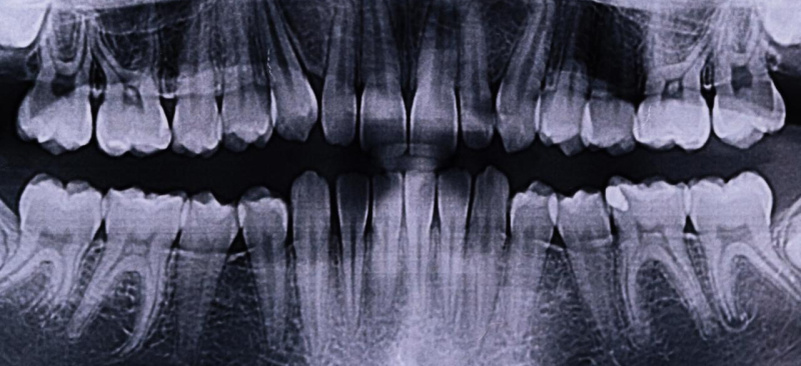

Ортопантомограмма: все о процедуре

Ортопантомограмма (ОПТГ) — это рентгеновский снимок, который позволяет получить полное изображение состояния зубочелюстной системы пациента. Этот метод активно используется в различных областях стоматологии, таких как ортодонтия, челюстно-лицевая хирургия и зубная имплантация. Для создания снимка применяется специализированное оборудование — ортопантомограф. В некоторых клиниках для этих целей используют компьютерные томографы, что позволяет получить более точное и детализированное изображение.

Что показывает ортопантомограмма?

Панорамный рентген позволяет выявить:

• аномалии зубочелюстной системы;

• кариес, в том числе на ранних стадиях;

• пародонтальные карманы;

• зубные кисты;

• воспалительные процессы.

С помощью ОПТГ можно определить:

• необходимость исправления неправильного прикуса;

• состояние тканей вокруг зубов;

• степень развития корней зубов;

• для установки имплантатов — состояние костной ткани в предполагаемом месте имплантации; и многое другое.